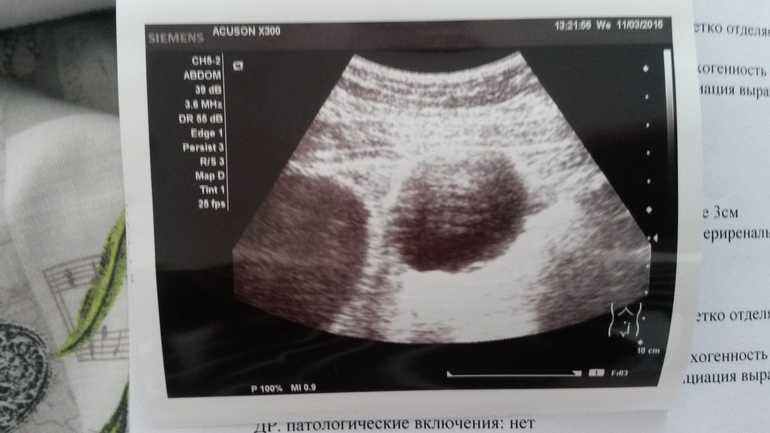

кто разбирается... фолликулярная киста или киста желтого тела?

Ориентируюсь на дни после овуляции. Сегодня где-то 10 дпо. Врач написала киста а сказала может и желтое тело...

Ну похожа на ЖТ, т.к неровный контур, у фоллика края ровные))) А кровоток есть? Обычно киста ЖТ бывает при Б, иногда просто)))

Размер 5.3 см. Врач написала что киста. Но не исключила желтое тело.